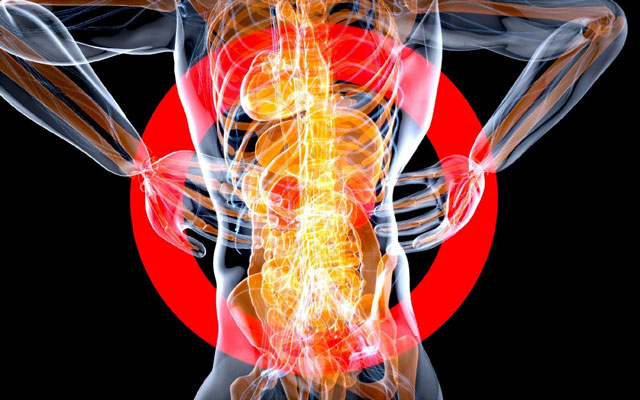

Back pain is such a commonly shared experience that it’s difficult to know when specialist care is needed.

If your pain lasts longer than a few days, despite taking proper care of yourself, that’s your first clue that your pain may not be what it seems. It could be due to a more complex issue with your nerves, bones, or soft tissue. In some cases, persistent back pain is a sign of a deeper neurological health problem.

When Pain Moves Beyond the Back

If your pain is spreading to other parts of your body, that’s cause for concern. This could mean a deeper issue with your nerves.

Radiculopathy is one such issue. A specialist can investigate if the nerve root in your spinal column is compressed or inflamed. Rather than a standard backache, radiculopathy pain is sharp with almost shock-like sensations. You may experience tingling or numbness in the arms and legs, as well.

Back pain can be a sign of neurological weakness, especially when it’s accompanied by stumbling or difficulty with lifting the front of your foot, known as foot drop. Saddle anesthesia can also occur, causing numbness in your inner thigh area.

Can Back Pain Become an Emergency?

If back pain is accompanied by loss of bowel or bladder control, that’s an emergency. It could be a sign of Cauda Equina Syndrome, which requires emergency surgery. This condition results from nerve root compression in the spinal cord.